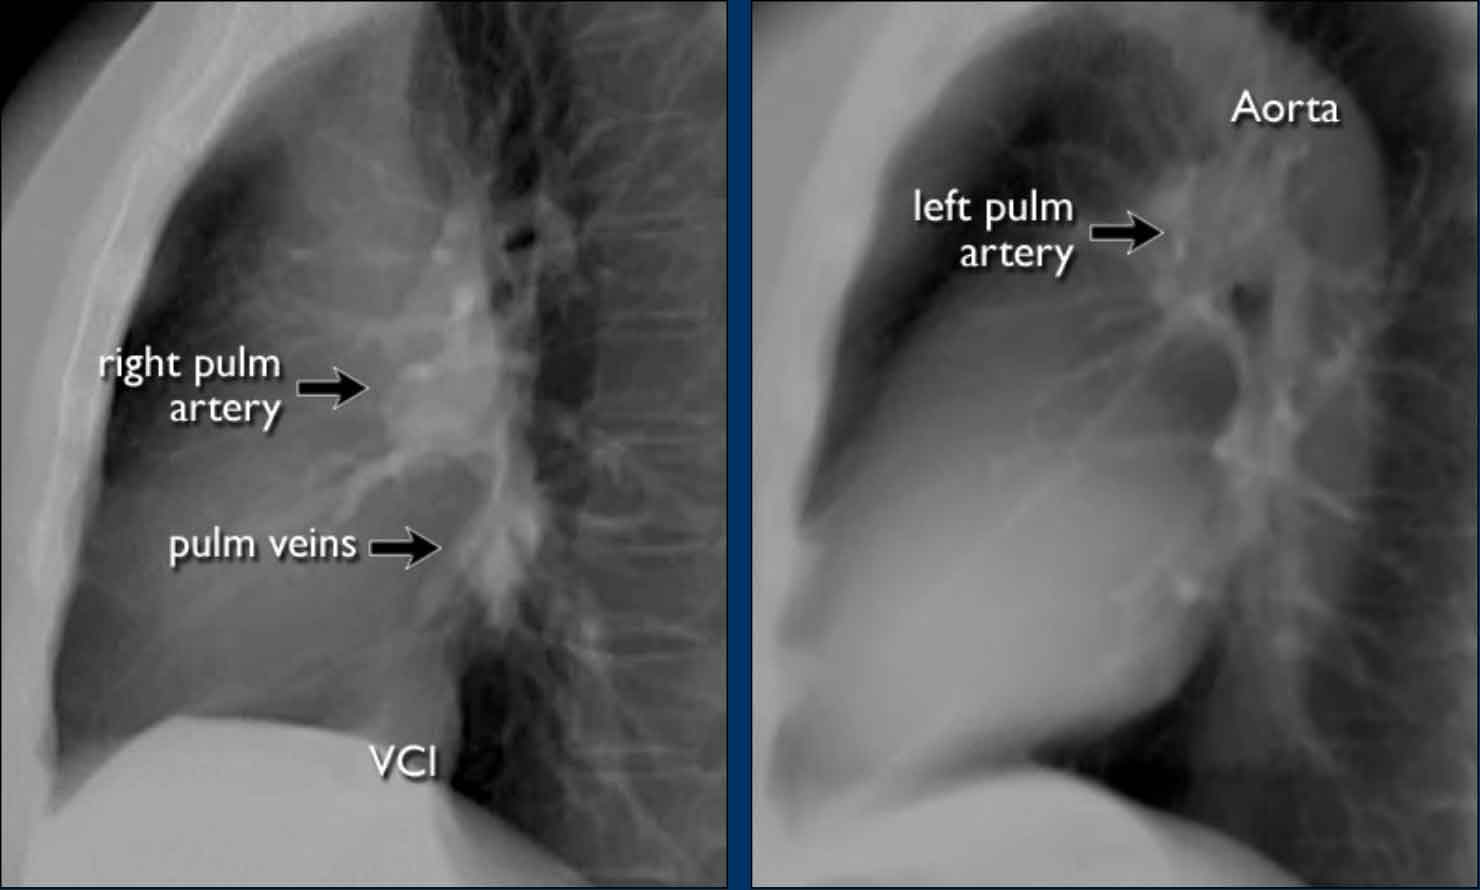

An important anatomical consideration is that the left hilum is normally situated higher than the right.

This relationship arises from the course of the pulmonary arteries: the left pulmonary artery arches over the left main bronchus, while the right pulmonary artery courses anterior to the right main bronchus, which is typically positioned lower than its left counterpart.

In a minority of cases, the hila may be at the same level, but the right hilum should never be higher than the left.

In this illustration, lower lobe pulmonary arteries are colored blue to indicate deoxygenated blood.

These arteries have a more vertical orientation compared to the pulmonary veins, which run more horizontally toward the left atrium, located inferior to the level of the main pulmonary arteries.

On lateral chest radiographs, both pulmonary arteries and veins are identifiable and should not be misinterpreted as lymphadenopathy. Occasionally, pulmonary veins may appear prominent.

The left main pulmonary artery passes superior to the left main bronchus and lies higher than the right pulmonary artery, which courses anterior to the right main bronchus.

The included images are thick-slab sagittal CT reconstructions of the thorax, which enhance visualization of hilar structures.

The lower lobe pulmonary arteries descend from the hilum in a vertically oriented fashion.

Radiographically, these vessels are colloquially referred to as the “little finger” due to their size and shape, approximating that of a little finger (1).

On PA chest radiographs, the "little finger" of the right lower lobe pulmonary artery is visible in approximately 94% of normal individuals, while on the left side it is visible in about 62% (1).